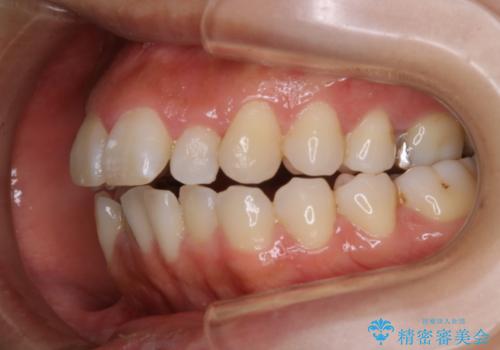

- 歯のガタつき、顎のズレ、出っ歯を気にして来院された患者様です。

歯を抜きたくないとの希望であったためマウスピース治療をお勧めしましたが、

マウスピースをずっとつけていることは難しいとの事であったためワイヤー矯正治療を行うこととなりました。